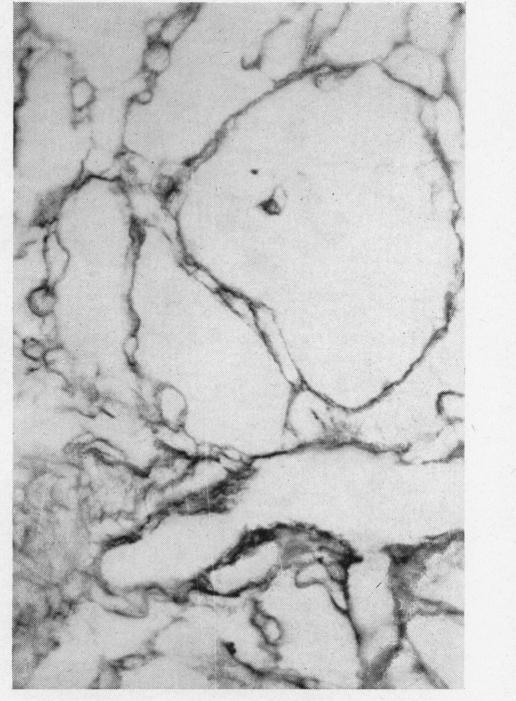

MALIGNANT NON-CHROMAFFIN PARAGANGLIOMA IN THE ORBIT.

Br J Ophthalmol. 1963 Jun;47(6):357-63. doi: 10.1136/bjo.47.6.357.